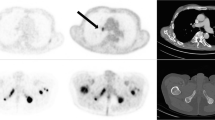

The pre- and post-therapy [68Ga]Ga-PSMA-11 PET/CT scans were analyzed applying a semiautomatic tumor segmentation algorithm using Syngo.Via (Enterprise VB 40B, Siemens, Erlangen, Germany) with a threshold of standardized uptake value (SUV) ≥ 3 as previously described by Ferdinandus et al. [34]. Physiologic [68Ga]Ga-PSMA-11 uptake sites such as the salivary glands, vocal cords, liver, spleen, intestine, ureter, and the bladder were manually excluded if these presented with an SUV above the threshold. For the segmentation of liver metastases, a threshold of 1.5 × SUVmean of the healthy liver tissue was used. Total lesion PSMA (TLP), defined as the summed products of volume × uptake (SUVmean) of all lesions, was calculated. Figure 1 illustrates the process of tumor delineation using Syngo.Via.

Example of tumor delineation using Syngo.Via. A Maximum intensity projection of [68Ga]Ga-PSMA-11 PET/CT. B PET/CT fusion (sagittal plane). C Tumor delineation in a sagittal PET slice with semiautomatically drawn volumes of interest (VOI). Tumor lesions are bordered violet (arrows point to exemplary bone lesions). Physiological uptake sites with green outline (arrows point to the liver and bladder) were manually excluded